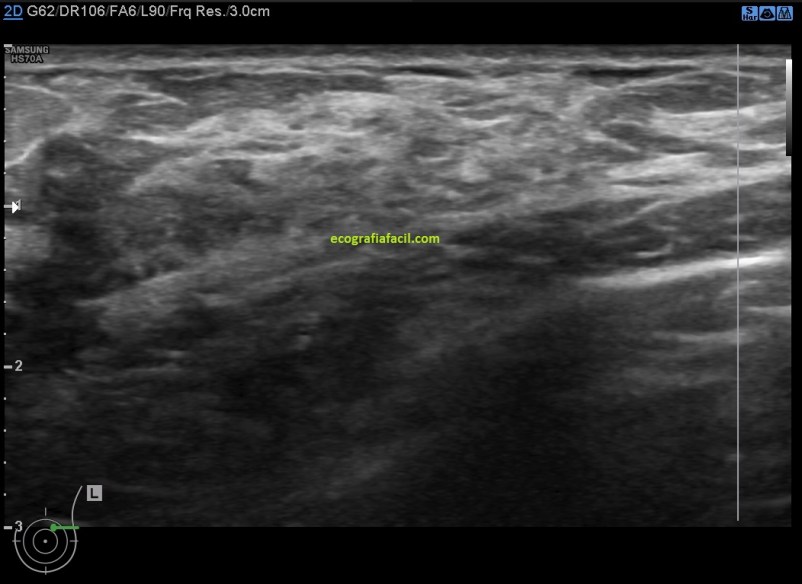

El estudio ecográfico mostró:

1. Mamas de predominio fibroso.

2. Acúmulos de tejido asímétricos de tejido fibroso de aspecto altamente denso e hipoecogénico de contorno mal definido en ambas mamas con ausencia de doppler color.

Imágenes:

4. Mastopatía Diabética

De la imagen 3 a la 6 tienes el aspecto semiolólogico normal de una mama diagnosticada de Mastopatía Diabética.